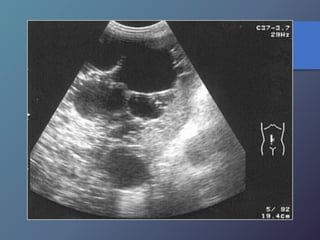

Enfermedad Poliquística

del Adulto

• Es autosómica dominante.

• Pruebas de función hepática normales.

• No se acompaña de fibrosis hepática ni

hipertensión portal.

Enfermedad Poliquística del Adulto •Es autosómica dominante. • Pruebas de función hepática normales. • No se acompaña de fibrosis hepática ni hipertensión portal.